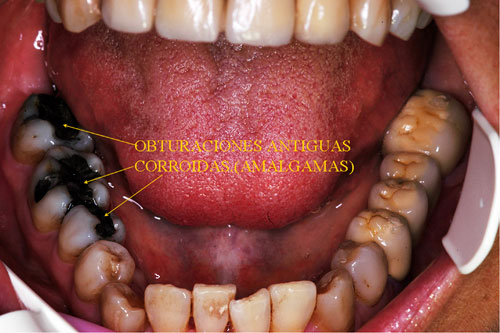

RESUMEN Mostración del Protocolo en R. O. y su desarrollo clínico. DESARROLLO Quienes realizamos Rehabilitación Bucal Integral desde muchos años atrás, siempre hemos buscado un protocolo coherente que nos permitiera ordenar el pensamiento cuando nos encontramos con aquellos caóticos casos donde marearse en la resolución es fácil y frecuente. PROTOCOLO DE ALONSO Sintéticamente consiste en otorgar al Sistema en primer término: Desoclusión en Lateralidades y Propulsiva de los sectores posteriores, mediante la construcción de la Guía Anterior tanto en los Provisorios como en los Definitivos, basados en el Encerado de Diagnóstico. PROTOCOLO PRÁCTICO (BASADO EN D.A.T.O.) Diagnóstico: clínico, radiográfico (donde no es necesario extenderse) y de laboratorio, donde mediante un encerado diagnóstico y otro de trabajo, conoceremos la fiel réplica de la boca del paciente antes de destruirse y los medios para reconstruirla basados en los procedimientos que podemos realizar en la cera. PRESENTACIÓN DEL CASO Se presenta la paciente derivada por un compañero a fin de consultar acerca de un primer molar superior izquierdo, a quien el Periodoncista aconsejaba realizar una radectomía debido a la pérdida ósea distal que dicha raíz presentaba. Dicha observación hace que decidamos tomar una actitud más conservadora, explicando al enfermo las razónes etiológicas de la pérdida ósea, y aconsejando quitar dicha funda para colocar una provisional morfológicamente correcta, y simultáneamente re-endodonciar y realizar la terapia básica periodontal. Visión Global del Caso Se observa a la inspección clínica y radiográfica, varios puentes fijos filtrados, como así también amalgamas de plata recidivadas. Inversión de la Curva de Wilson.(2º Elemento a nuestro alcance para obtener Desoclusión Se procede entonces luego de realizar los correspondientes modelos de yeso mediante impresiones precisas de alginato con cubetas Rim Lock, a tomar un registro cráneo maxilar mediante un arco facial estático (Artex) que nos permita montar el modelo superior respecto del Plano de Frankfurt con el punto Gnation de referencia. Luego, haciendo uso de las Laminillas de Long , (buscar referencias en el libro del Dr. Alonso o bien en múltiples publicaciones personales en Gaceta Dental o Maxillaris, como así también en mi propia web: en los artículos : RELACIÓN CÉNTRICA o AJUSTE OCLUSAL, BASES FILOSÓFICAS DE UNA OCLUSIÓN ORGÁNICA), (www.dracuna.com o www.oclusión.es,) . Procedemos a obtener el Registro Inter Maxilar de OCLUSIÓN EN RELACIÓN CÉNTRICA, mediante el cual, montamos el modelo inferior respecto del superior. Montamos así, en un Artex totalmente ajustable, pués no contábamos en ese momento con ningún semiajustable disponible,(ya que estaban todos ocupados), ajustando el Ángulo de Bennet y la Inclinación de la Trayectoria Condílea en gradaciones personalizadas mediante registros de Propulsión y Lateralidades). Procedemos entonces al estudio de los modelos. DIAGNÓSTICO GENERAL Disfunción oral generalizada, provocada por alteraciones en la Oclusión, en la Operatoria Dental, en la Endodoncia, en la Periodoncia y en la Prótesis realizada en esta boca a través de los años. Filtración generalizada de fundas. DIAGNÓSTICO PROTÉTICO OCLUSAL Carencia de guía canina. Carencia de alineación tridimensional en guía anterior. Carencia de curva de Wilson. TRATAMIENTO SUGERIDO 1-Encerado Progresivo de Diagnóstico y Trabajo de Peter K. Thomas. HEMOS OBTENIDO: D.AT.O Hasta aquí, hemos solo observado los elementos de diagnóstico clínicos, radiológicos y de laboratorio, como para comenzar a trabajar. AUTOR: Colaboración: CASO PRESENTADO EN LAS SESIONES CLÍNICAS DEL ILTRE. COLEGIO DE DENTISTAS DE MÁLAGA. Ratificación del Protocolo en Rehabilitación Bucal a pesar de las incidencias propias de cada caso clínico. A propósito de un caso.

Amalgamas Desbordantes/Reabsorción Ósea Horizontal en 6-5 y Vertical en 6-7

3-Remoción completa de Puentes y Amalgamas carentes de funcionalismo.